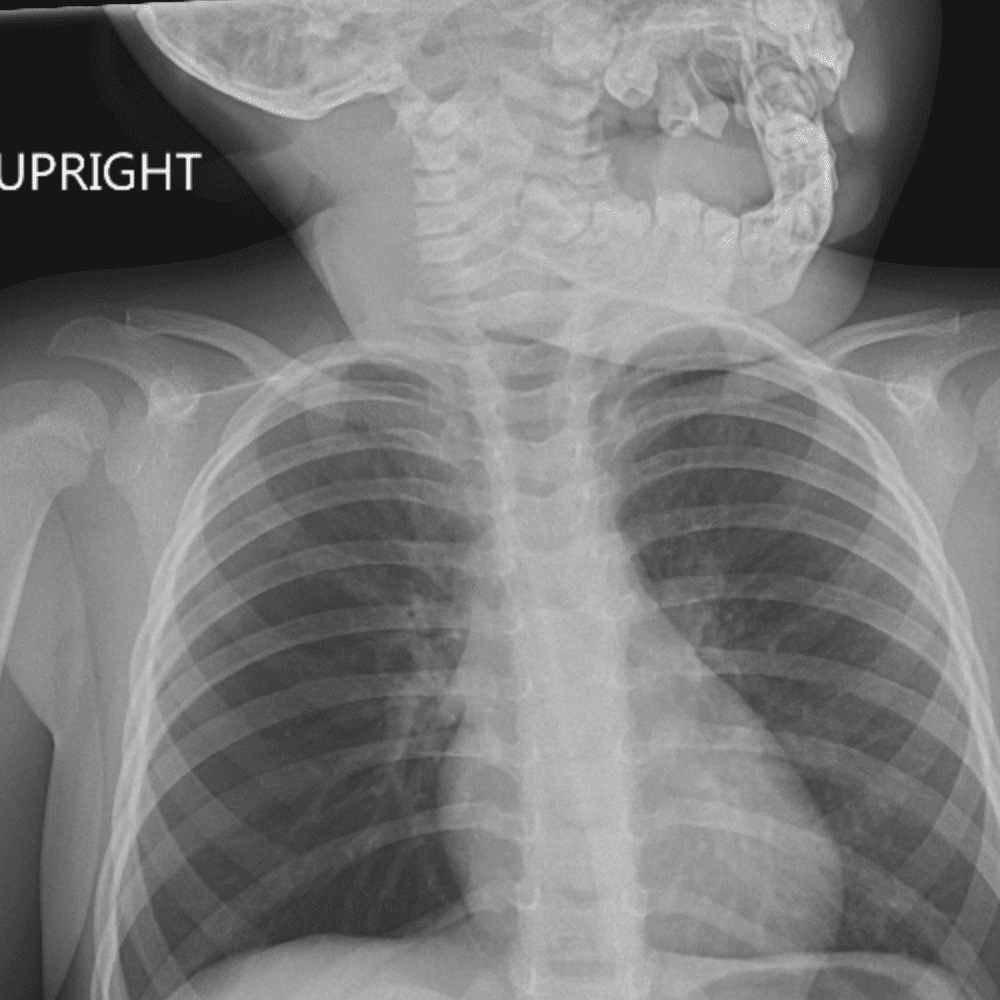

Peds Chest

Practice

Simulates call by including subtle or difficult cases and some normals.

50 cases